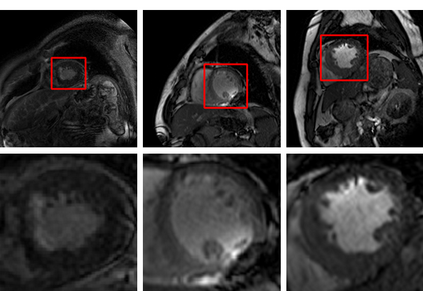

Multi-sequence cardiac magnetic resonance (CMR) provides essential pathology information (scar and edema) to diagnose myocardial infarction. However, automatic pathology segmentation can be challenging due to the difficulty of effectively exploring the underlying information from the multi-sequence CMR data. This paper aims to tackle the scar and edema segmentation from multi-sequence CMR with a novel auto-weighted supervision framework, where the interactions among different supervised layers are explored under a task-specific objective using reinforcement learning. Furthermore, we design a coarse-to-fine framework to boost the small myocardial pathology region segmentation with shape prior knowledge. The coarse segmentation model identifies the left ventricle myocardial structure as a shape prior, while the fine segmentation model integrates a pixel-wise attention strategy with an auto-weighted supervision model to learn and extract salient pathological structures from the multi-sequence CMR data. Extensive experimental results on a publicly available dataset from Myocardial pathology segmentation combining multi-sequence CMR (MyoPS 2020) demonstrate our method can achieve promising performance compared with other state-of-the-art methods. Our method is promising in advancing the myocardial pathology assessment on multi-sequence CMR data. To motivate the community, we have made our code publicly available via https://github.com/soleilssss/AWSnet/tree/master.